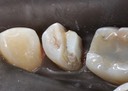

Joe Cha #18 amalgam removal

Joe Cha #18 prep